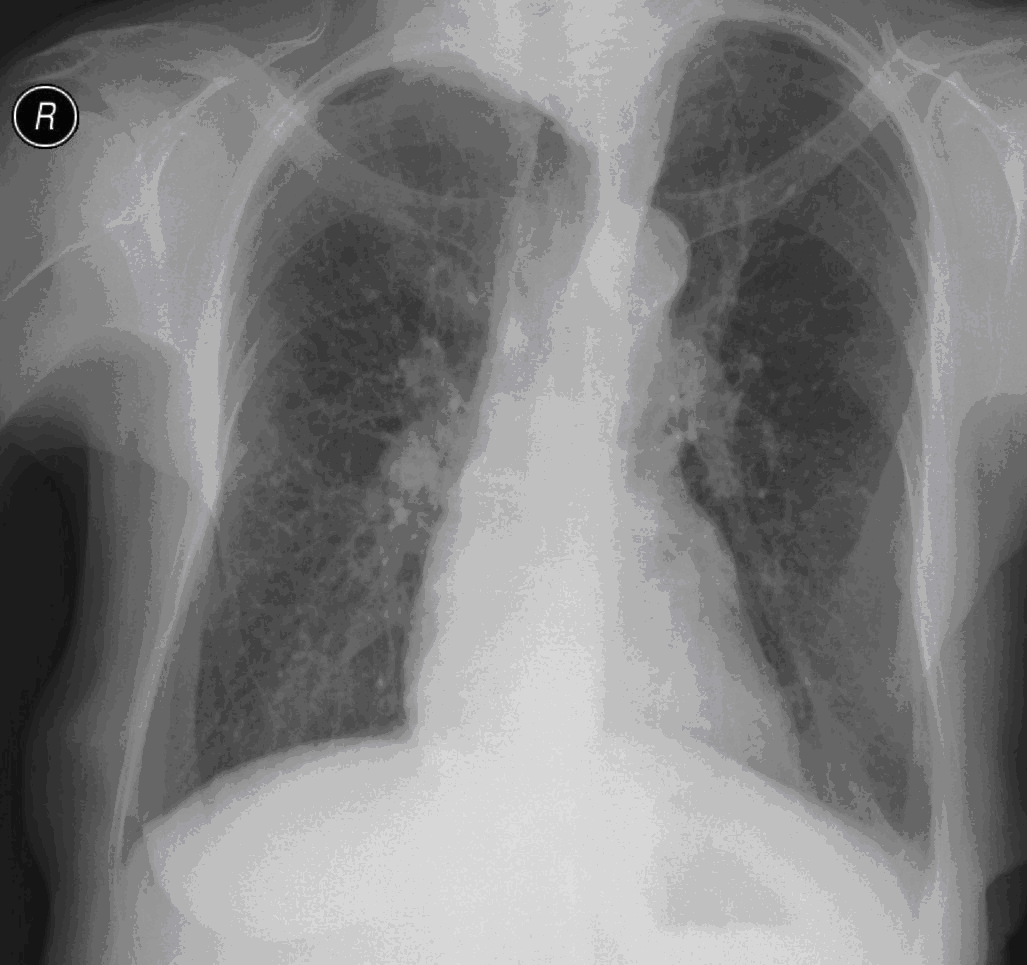

23. Pulmonary metastases, bidirectional (PA and right lateral) plain chest radiograph.

51 year old woman, endometrial carcinoma. Numerous ring shadows bilaterally in basal dominance (max. appr. 12 mm). Left pleural effusion of one finger wide.